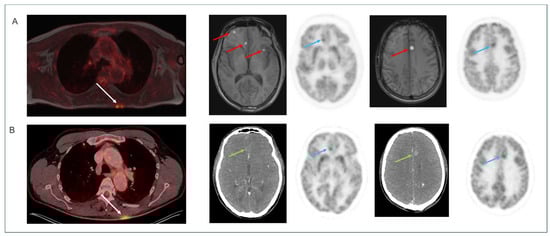

First Clinical Experiences with the Ultra-Fast Time-of-Flight BIOGRAPH One Next-Generation Hybrid PET/MRI System

by Otto M. Henriksen, Kirsten Korsholm, Annika Loft, Johanna M. Hall, Annika R. Langkilde, Vibeke A. Larsen, Thomas S. Kristensen, Caroline Ewertsen, Frederikke E. Høi-Hansen, Patrick M. Lehmann, Karen Kettless, Flemming L. Andersen, Thomas L. Andersen and Ian Law

Diagnostics 2026, 16(3), 398; https://doi.org/10.3390/diagnostics16030398 - 27 Jan 2026

Objective: We present the first clinical experience with the BIOGRAPH One next-generation PET/MRI system scanner, evaluating its performance for body and brain imaging in patients across multiple tracers. Methods: A total of 59 patients were scanned on the BIOGRAPH One PET/MRI following standard clinical PET/CT (n = 52) or first-generation PET/MRI (Biograph mMR, n = 7). Scans comprised 30 total body (TB), whole body (WB), or regional scans with [18F]FDG, and 29 brain scans with either [18F]FDG (n = 5), [18F]FE-PE2I (n = 10), [18F]FET (n = 4), or [68Ga]Ga-DOTATOC (n = 10). The PET image quality was visually assessed using a 5-point Likert scale (1 = very good to 5 = very bad) and compared with clinical scans acquired on either a current-generation digital PET/CT or a first-generation PET/MRI system, including evaluation of diagnostic concordance. PET quantification and image noise was compared in brain and WB/TB [18F]FDG PET scans. Results: PET image quality was rated as good or very good in 93% of scans with a median [inter-quartile range] score of 1.5 [1.5;2]. In 99% of cases, image quality was judged equal to or better than the clinical reference scan (median score 3 [2.5;3]). Diagnostic concordance was observed in 99% of readings. Imaging metrics revealed the anticipated regional bias in brain imaging, while no significant bias was observed in body imaging. Image noise was comparable to that observed with digital PET/CT and demonstrated superiority over first-generation PET/MRI despite potential degradation related to isotope decay in BIOGRAPH One PET/MRI acquisitions scans performed at the end of the imaging workflow. Conclusions: Within the study limitations related to sequential imaging, the BIOGRAPH One PET/MRI scanner demonstrated improved PET sensitivity and workflow potential over its first-generation predecessor, which may allow for broader clinical and research applications. Full article